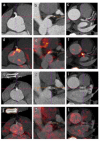

The method of 18F-sodium fluoride (NaF) positron emission tomography/computed tomography (PET/CT) of atherosclerosis was introduced 12 years ago. This approach is particularly interesting because it demonstrates microcalcification as an incipient sign of atherosclerosis before the development of arterial wall macrocalcification detectable by CT. However, this method has not yet found its place in the clinical routine. The more exact association between NaF uptake and future arterial calcification is not fully understood, and it remains unclear to what extent NaF-PET may replace or significantly improve clinical cardiovascular risk scoring. The first 10 years of publications in the field were characterized by heterogeneity at multiple levels, and it is not clear how the method may contribute to triage and management of patients with atherosclerosis, including monitoring effects of anti-atherosclerosis intervention. The present review summarizes findings from the recent 2¾ years including the ability of NaF-PET imaging to assess disease progress and evaluate response to treatment. Despite valuable new information, pertinent questions remain unanswered, not least due to a pronounced lack of standardization within the field and of well-designed long-term studies illuminating the natural history of atherosclerosis and effects of intervention.